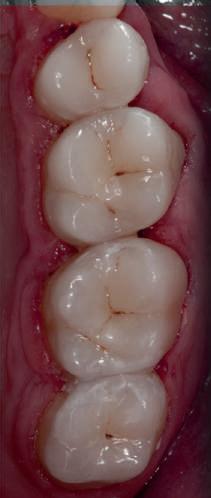

Fig. 1 prezintă pacientul după inserarea primului set de bonturi implantare individualizate; dinţii naturali adiacenţi

sunt încă prezenţi pentru a susţine puntea provizorie.

Şapte luni mai târziu (fig. 2), acele bonturi individualizate din prima etapă au manifestat semne de recesie de 1-3mm. Atitudine: S-a decis reprepararea intraorală a tuturor bonturilor (fig. 3), astfel încât toate marginile bonturilor să fie la nivelul sau sub marginea gingivală (de notat că 1.1. şi 2.1. au fost submersaţi ulterior pentru a avea sprijin implantar deplin).

Deşi reprepararea a îmbunătăţit marcat estetica finală, a necesitat aplicarea şnurului de retracţie, amprente noi şi turnări noi.

Un caz separat dar similar ilustrează în figurile 4 și 5 reprepararea intraorală a bontului.

Cazul (1): Reprepararea intraorală a bonturilor Figurile

1. Aspect după inserarea primului set de bonturi implantare individualizate.

2. După 7 luni, bonturile individualizate din prima etapă au prezentat recesie de 1-3mm.

3. Bonturile repreparate intraoral.

Alt caz (1) Figurile

4. După osteointegrarea implantului 2.4., s-a observat recesia în etapa de amprentare a implantului 2.5.; s-a decis reprepararea marginilor bontului individualizat CAD/CAM 2.4. Înainte de preparare s-a aplicat şnur de retracţie pentru a evita lezarea ţesutului şi a îmbunătăţi vizibilitatea dintelui 2.3. şi a marginii bontului implantar individualizat. Aşa cum era de aşteptat, recesia a fost mai mare de-a lungul versantului distal al bontului 2.4. adiacent locului de extracţie vindecat/cu implantul mai nou.

5. Bontul individualizat aplicat (2.5.) cu bontul repreparat anterior (2.4.). Nu a survenit recesie nouă de o perioadă de peste 3 ani.